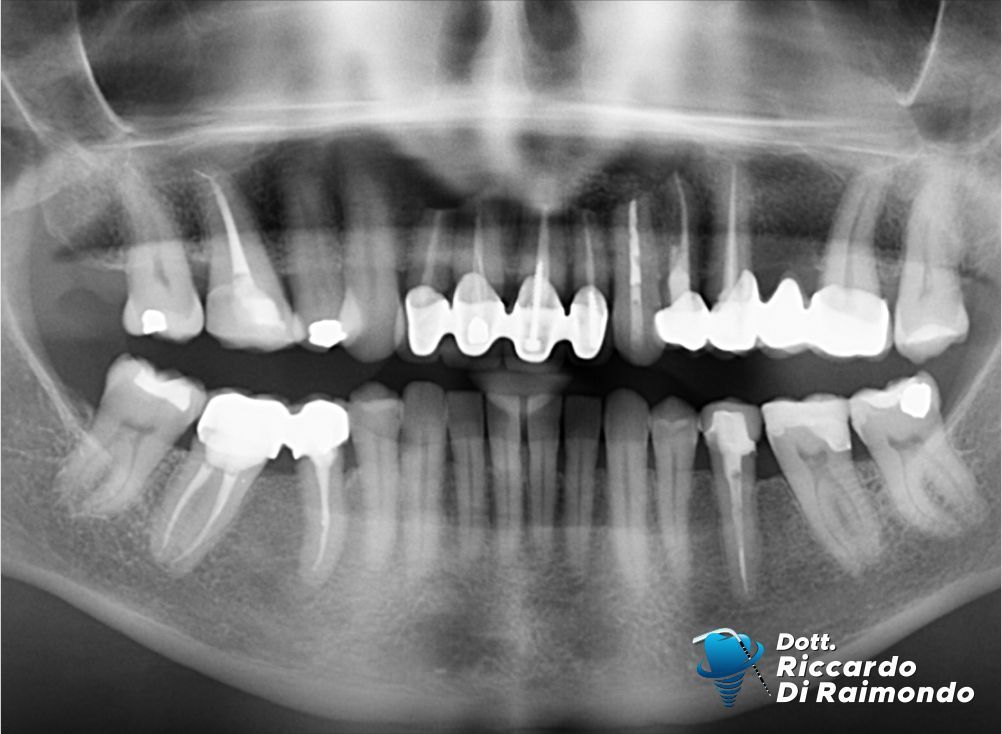

Rimozione cisti mascellare superiore frontale

Prima del trattamento